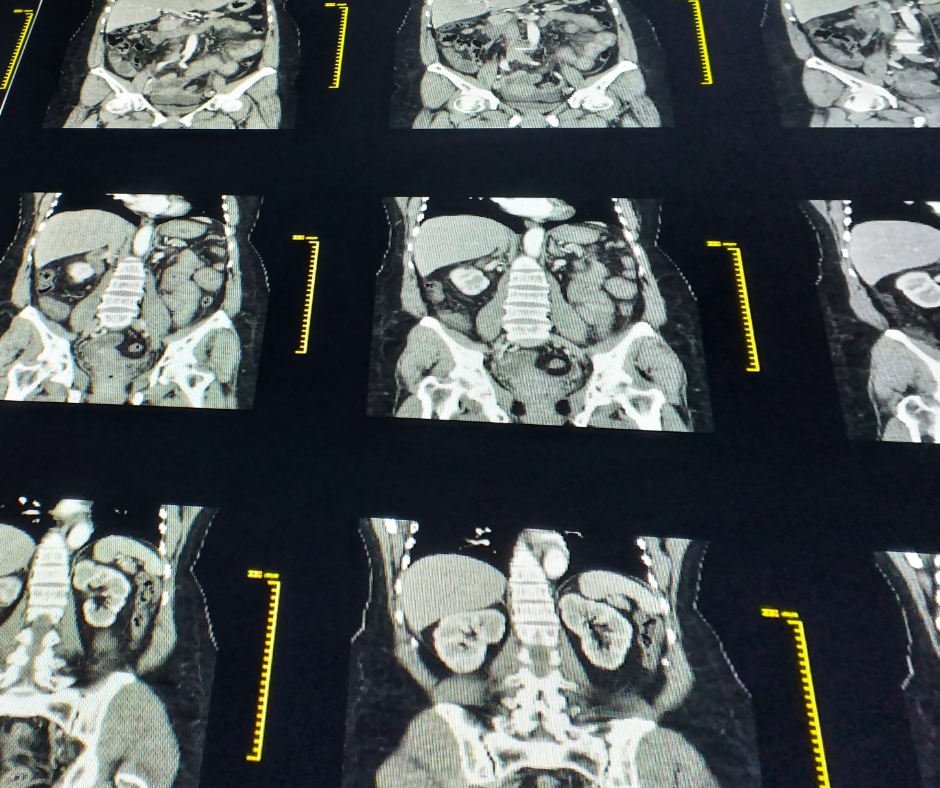

What Is CT Scan Bloggjhedu